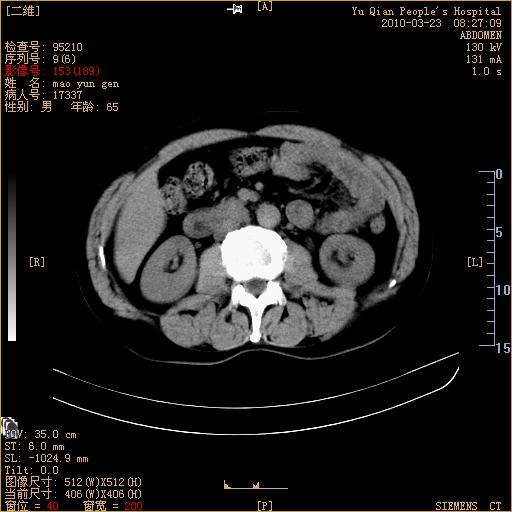

标题: CT25266:消瘦月余,前来肝部检查,请看看肠腔 [打印本页]

标题: CT25266:消瘦月余,前来肝部检查,请看看肠腔

肝区结肠占位,腺癌可考虑,建议肠镜活检。

升结肠肠壁增厚,不均强化,考虑升结肠腺癌可能性,建议肠镜检查。

1)考虑升结肠癌。2)右肾小囊肿。